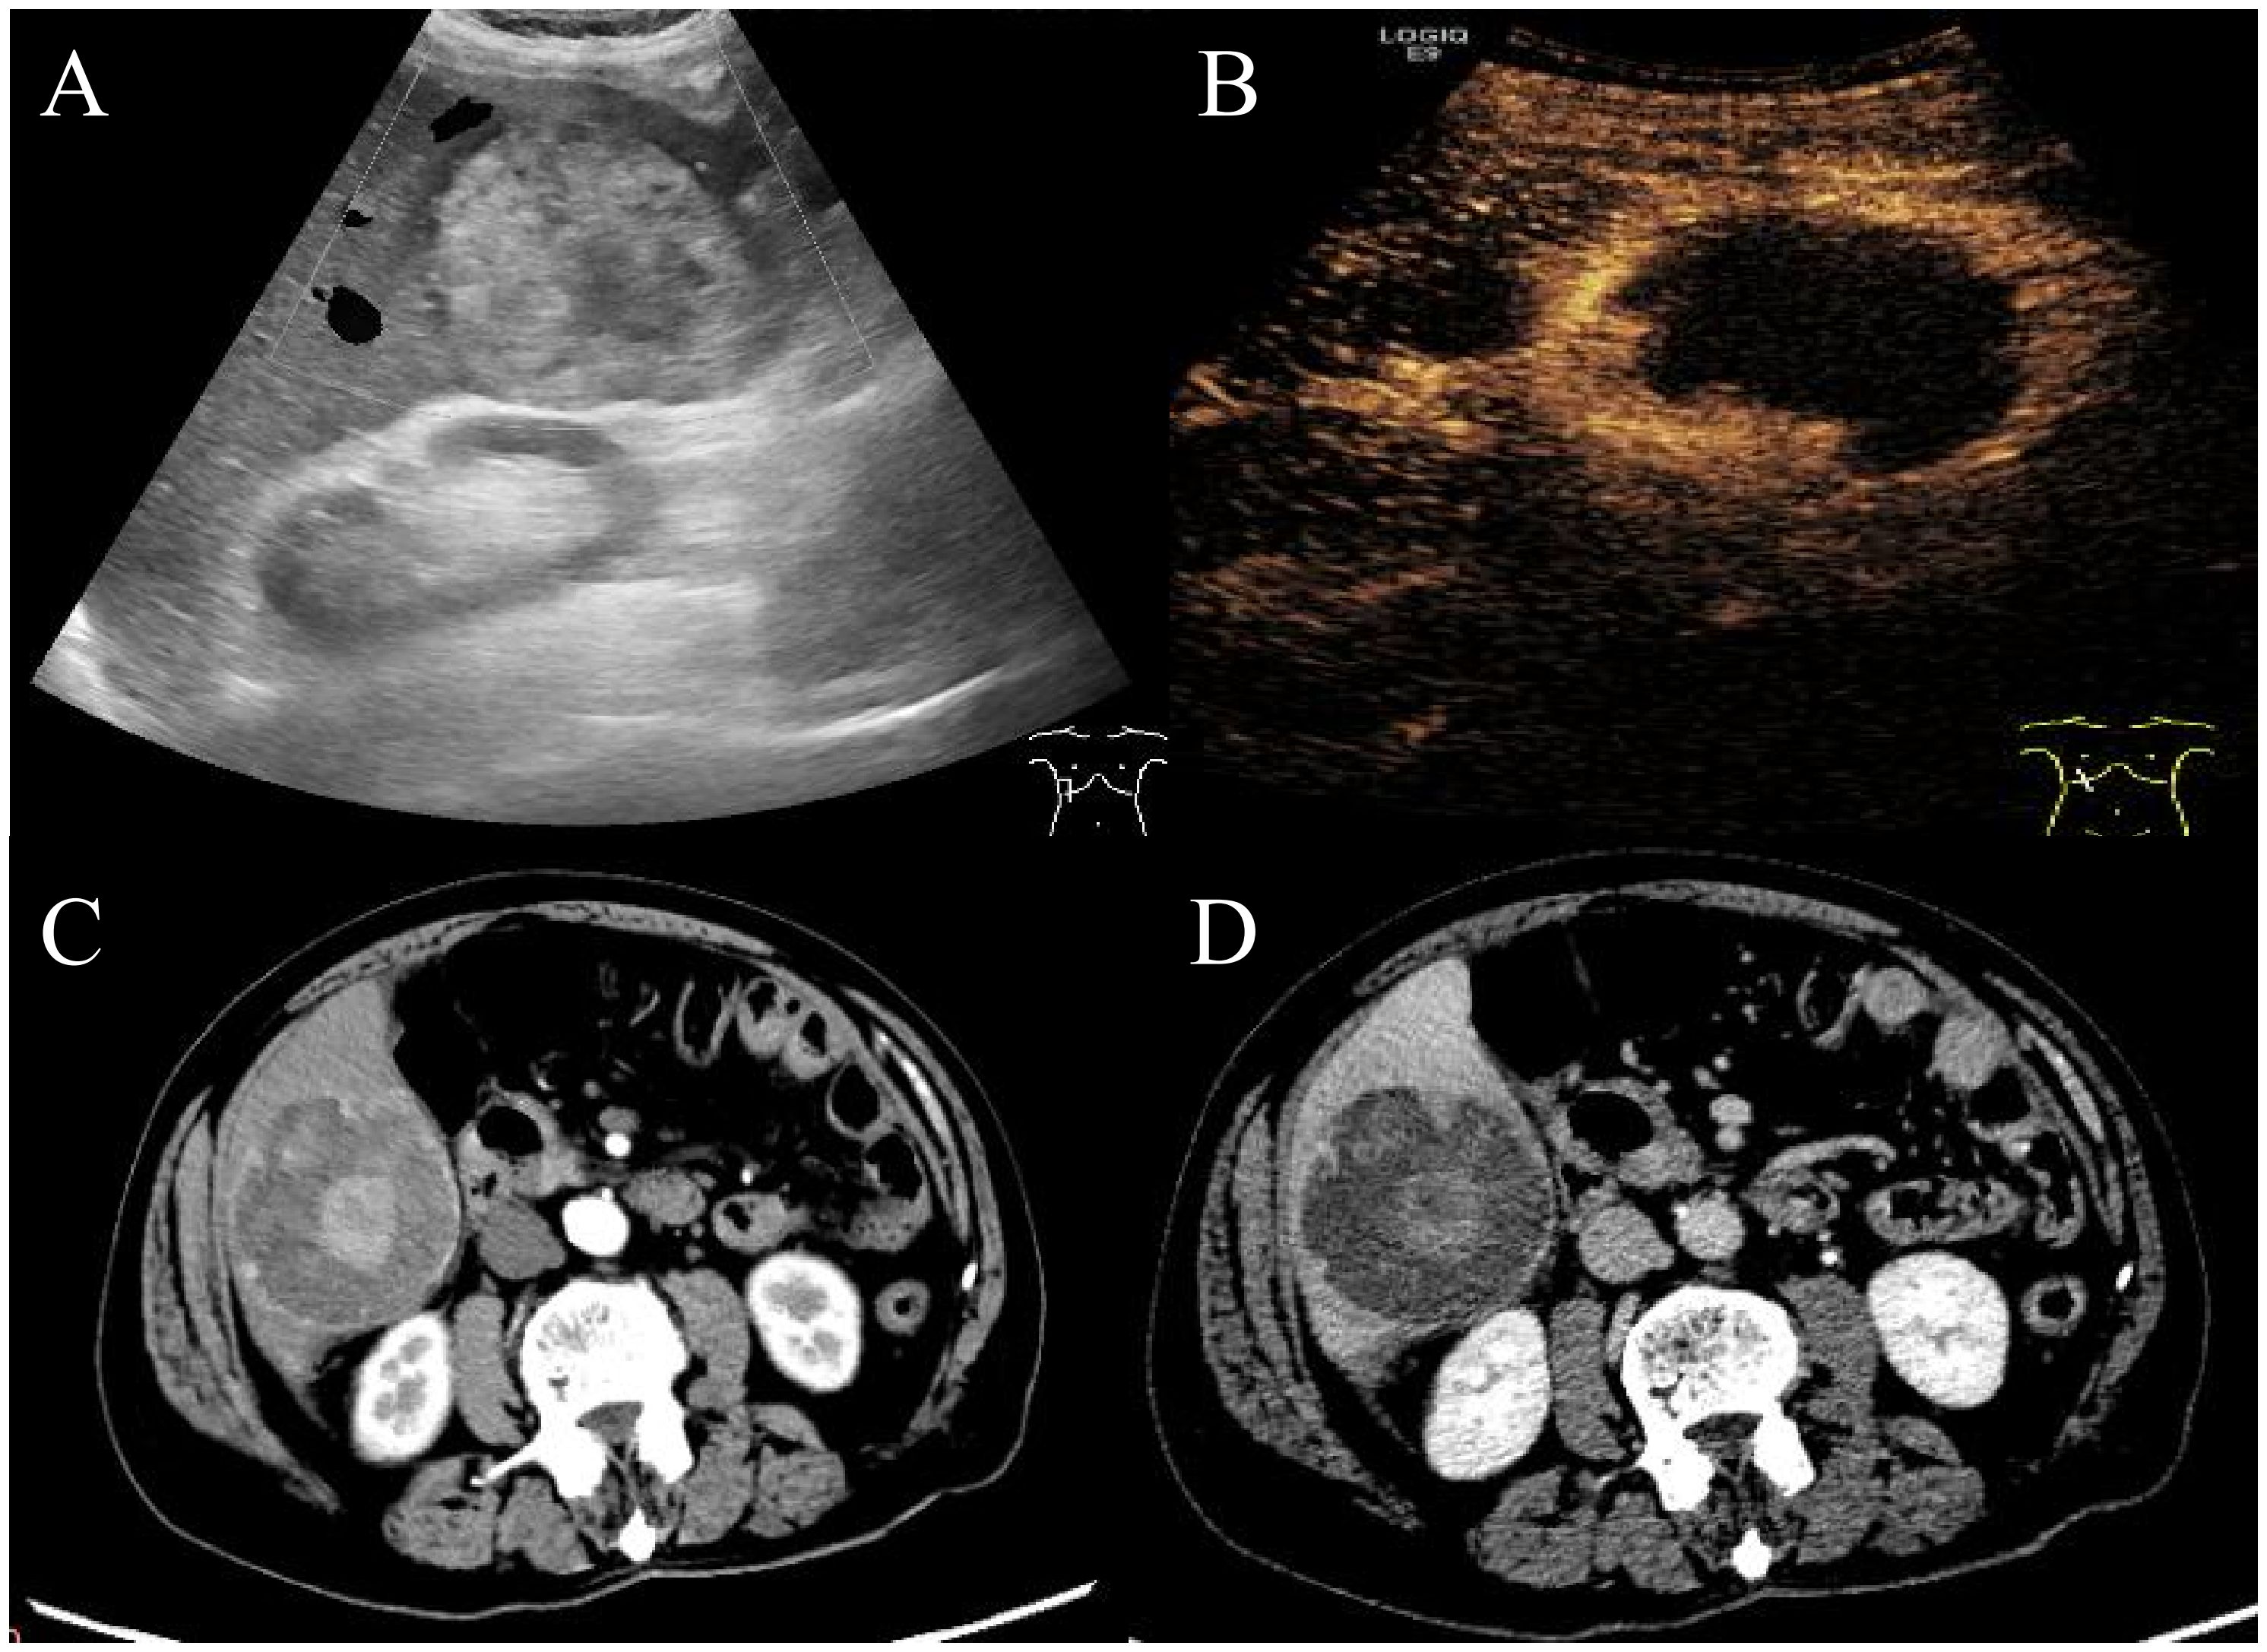

Pembrolizumab combined with surgical treatment for spontaneously ruptured undifferentiated pleomorphic sarcoma of the liver: A case report and literature review

Undifferentiated pleomorphic sarcoma of the liver (UPSL) is a rare pathological type characterized by an undefined mechanism, low incidence, high metastatic rate, aggressive behavior, and an inferior prognosis; no standardized treatment protocols or guidelines currently exist. This article reports the case of an 83-year-old male with UPSL confirmed through surgical resection and pathological biopsy. Postoperatively, he received eight cycles of pembrolizumab, which resulted in a favourable clinical efficacy. With advances in medical technology, the integration of surgery and immunotherapy is expected to play an essential role in treating this rare disease and monitoring its prognosis.